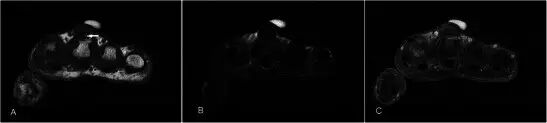

血管瘤 Haemangiomas 血管瘤是第四最常见的手部肿瘤,通常发生在年轻的年龄组,有轻微的女性优势[27]。在MR上,它们通常在T2w序列上非常高信号,并且显示出小叶,间隔或低信号灶比其他软组织块更频繁[28]。 T2w序列上损伤的标记高度信号是由于血管中停滞血流量增加的流体含量。 由于存在脂肪和血液成分,T1w序列上的信号通常与肌肉相比具有高信号(图8)。 通常大于2cm的损伤含有不同量的脂肪,平滑肌,粘液样基质,血栓和血铁素。上的GRE序列容易产生的假象可能是由于静脉石或血液成分引起,并且这些可以在平片进行区分。较大的病变也可能表现出流体 - 液体水平[29]。延时增强后瘤体趋于均匀强化。浅表性血管瘤易于诊断,因为皮肤褪色的存在,并且MRI可能仅需要评估其手术规划的程度。

图8.32岁女性血管瘤,沿着右手掌侧的内侧面呈现软肿块,偶尔会疼痛。 (a)T1w序列显示多发性皮下病变,小鱼际肌稍高信号肌肉,相邻肌腱(箭头)之间, 有一个小的肌肉内占位(箭头)。 (b)病灶在具有低信号(箭头)区域和流体 - 液体水平(箭头)建议的T2w-FS序列上是极度高信号的。 (c)看到显示静脉石或血制品(箭头)GRE序列。 (d)有积极和接近均匀的增强(箭头)